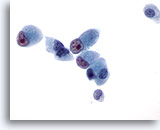

画像 2: 肝FNA – 良性肝細胞

反応性変化を来した良性肝細胞の集塊。細胞境界が明瞭な立方形の細胞が認められます。不透明な細胞質には空胞が認められるものもあれば、幾分顆粒状を呈するものもみられます。辺縁部は擦り切れた状態を呈しています。核はわずかに大小不同で、二核を有する細胞も認められます。小型の核小体がみられます。

40倍

画像 2

肝FNA – 良性肝細胞

反応性変化を来した良性肝細胞の集塊。細胞境界が明瞭な立方形の細胞が認められます。不透明な細胞質には空胞が認められるものもあれば、幾分顆粒状を呈するものもみられます。辺縁部は擦り切れた状態を呈しています。核はわずかに大小不同で、二核を有する細胞も認められます。小型の核小体がみられます。

40倍